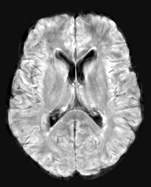

The detection of new multiple sclerosis (MS) lesions is an important marker of the evolution of the disease. The applicability of learning-based methods could automate this task efficiently. However, the lack of annotated longitudinal data with new-appearing lesions is a limiting factor for the training of robust and generalizing models. In this work, we describe a deep-learning-based pipeline addressing the challenging task of detecting and segmenting new MS lesions. First, we propose to use transfer-learning from a model trained on a segmentation task using single time-points. Therefore, we exploit knowledge from an easier task and for which more annotated datasets are available. Second, we propose a data synthesis strategy to generate realistic longitudinal time-points with new lesions using single time-point scans. In this way, we pretrain our detection model on large synthetic annotated datasets. Finally, we use a data-augmentation technique designed to simulate data diversity in MRI. By doing that, we increase the size of the available small annotated longitudinal datasets. Our ablation study showed that each contribution lead to an enhancement of the segmentation accuracy. Using the proposed pipeline, we obtained the best score for the segmentation and the detection of new MS lesions in the MSSEG2 MICCAI challenge.